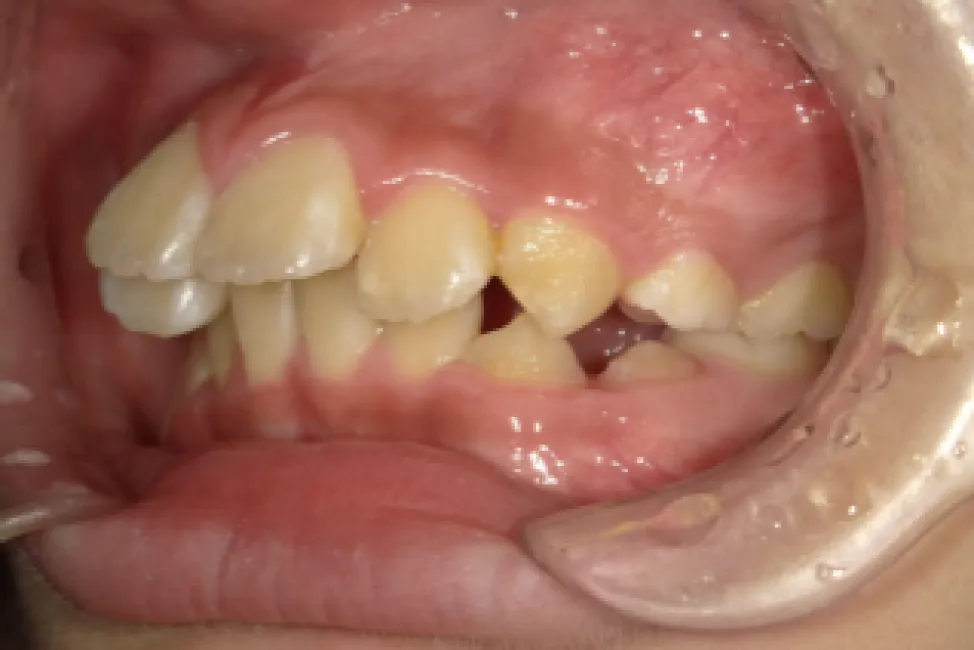

Before

After

性別

年齢

治療費用

治療内容

リスク

副作用

治療期間

男性

小学校高学年

902,000円

1年9か月

インビザライン

矯正治療の一般的なリスクといた

しましては、治療中のお痛み・歯

根吸収・歯肉退縮・治療後の後戻

りなどが生じる可能性があります。矯正治療は始めると、元の状態に

戻すのが難しいことがあります。